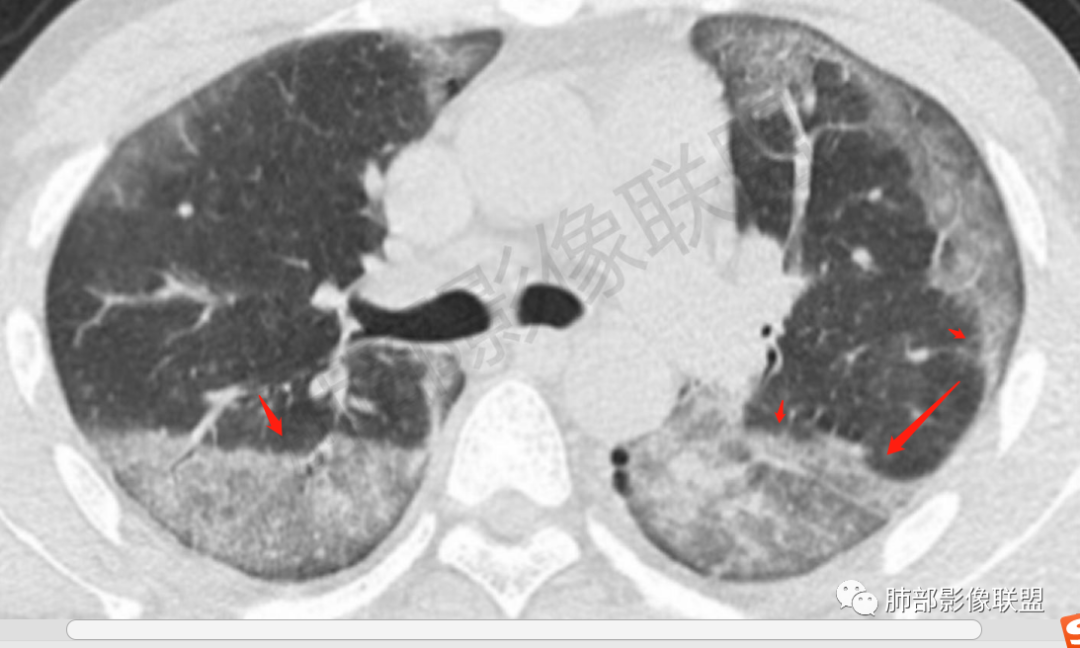

小兜:男,34岁,急性病容,临床症状进展快,双肺早期CT可见少量磨玻璃影,四天后复查进展迅速,双侧对称胸膜下为主,双下肺为重,对症治疗效果不佳,考虑中毒所致,百草枯可能

一切∮随缘:第一次CT双肺弥漫小结节,密度较淡,间隔4天后,双肺弥漫性渗出及间质增厚,以胸膜下及下肺为主,部分伴有重力作用,临床症状较重,考虑AIP,ARDS?重症结核?

宇宙:初次CT两肺纹理模糊,4天后进展迅速,两肺弥漫磨玻璃影,两肺外周及下叶胸膜下为主,与正常肺组织分界清,心影增大,支持百草枯中毒

爱跳舞的猫:两肺快速进展弥漫磨玻璃影,两肺外周及下叶胸膜下为主,小叶间隔增厚,上肺反晕征,支持百草枯中毒

病灶进展迅速

分布外周胸膜下

GGO+网线

网格——间质改变

边缘线影

提示边缘修复,有OP样改变

1.双肺病灶从无到有,进展迅速,沿胸膜下分布磨玻璃密度为斑片影,较均匀,边界较清楚,呈镰刀状,近乎对称,期间可见细网格,符合较典型百草枯中毒肺影像学表现。